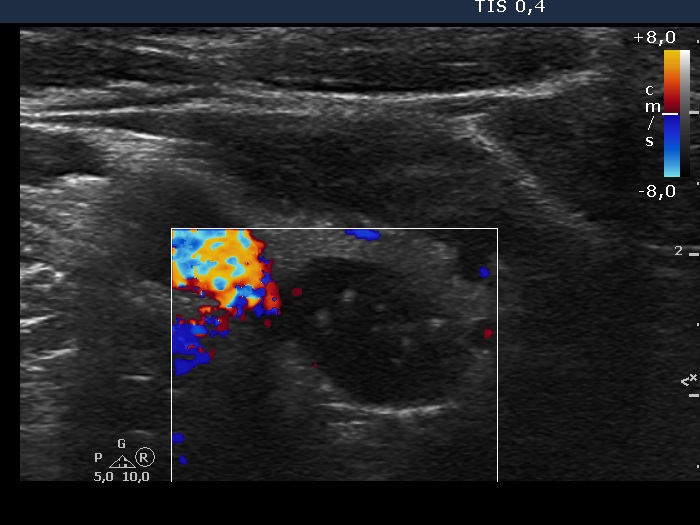

Intranodular hyperechogenic figures - case 284 (ultrasonographic picture 6)

Right lobe, horizontal view, color Doppler mode, enlargement. The form of the colloid crystals are typical while they are less bright than in usual cases.